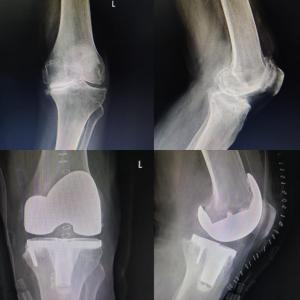

Orthopedic

Revision Knee & Hip Replacement

Complex Joint Replacement Surgery